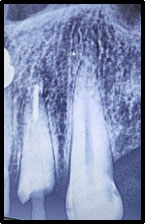

It was recommended that the patient undergo root canal therapy, a post and core build-up, and finally a final crown restoration. After administering local anesthesia, an endodontic access cavity was created, the canal orifices were identified, and the working length was established. The canal was biomechanically prepared up to size 25 with a 0.06 taper, followed by obturation using the single-cone technique in conjunction with AH Plus sealer (Fig. 2).

PRE-operative radiograph.